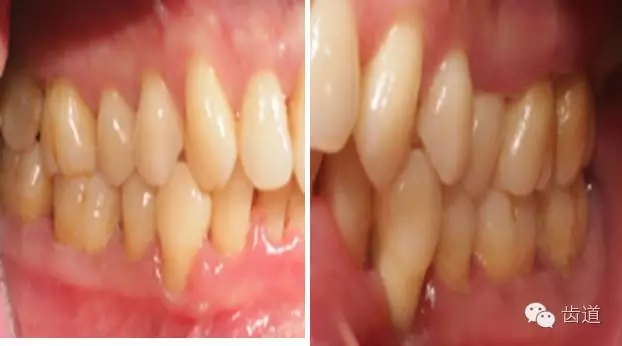

2、牙齦

(顏色、形狀、質(zhì)地、退縮、BOP、PD、附著齦)